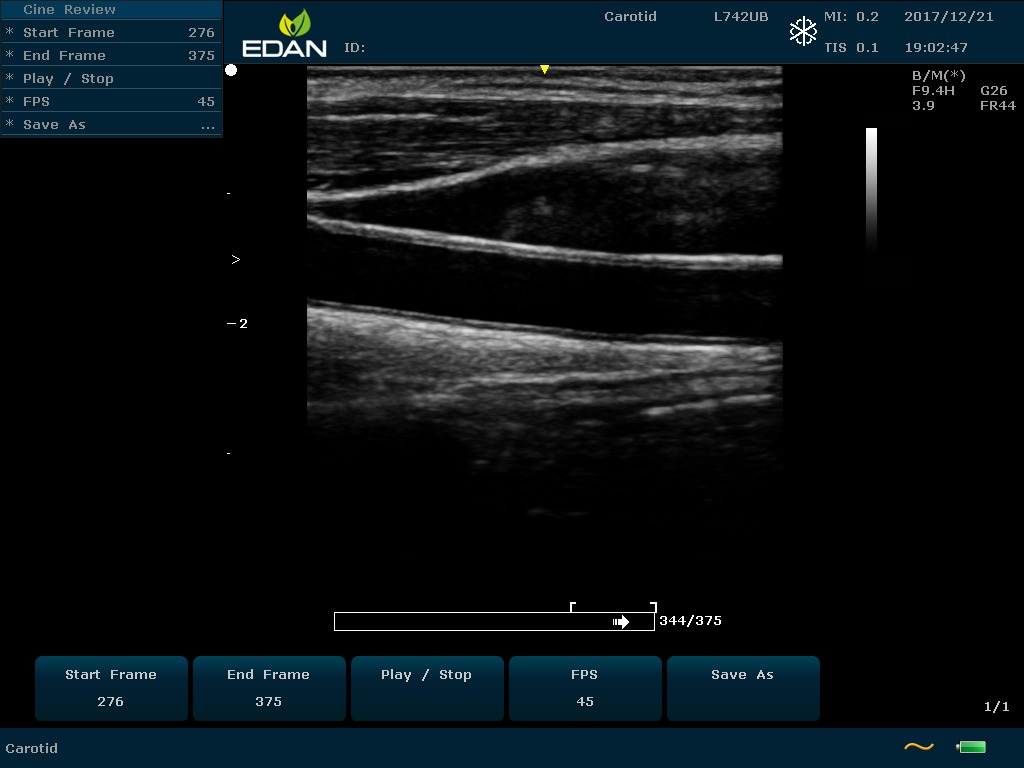

Особенность U60 Edan — расширенное применение. Ультразвуковой аппарат рекомендован для абдоминальных исследований, гинекологии и акушерства, кардиологии, педиатрии, урологии, изучения малых органов, сосудов. Для U60 Edan используются конвексные, линейные, фазированные и внутриполостные датчики.

Передовые технологии позволяют повысить качество визуализации в несколько раз. УЗИ-аппарат U60 Edan отличается возможностью быстрой настройки визуализации. Специальные функции позволяют моментально отображать данные за счет быстрой оптимизации параметров. Режимы визуализации: B-mode, M-mode, Color Doppler, Power Doppler Imaging, Pulsed Wave Doppler, Continuous Doppler.